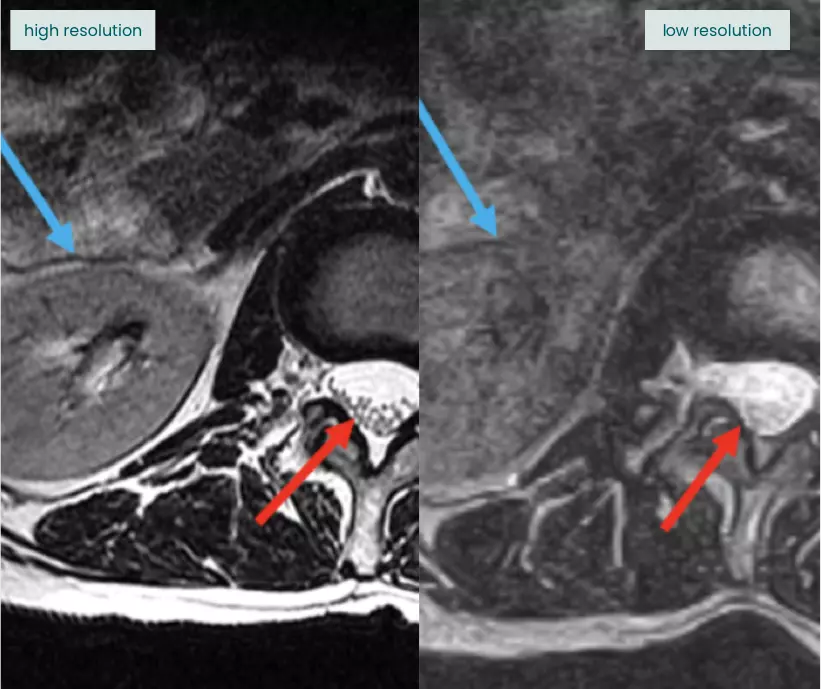

Errors in interpretation can send patients down the wrong treatment path.

Failure to describe the muscle atrophy accompanying this rotator cuff tear represents a missed chance to flag that the patient may be a poor candidate for surgery and unlikely to recover well.

Atrophied

Normal